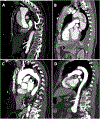

Purpose of review: Acute aortic syndromes, including aortic dissection, intramural hematoma, and penetrating aortic ulcer, are a group of highly morbid, related pathologies that are defined by compromised aortic wall integrity. The purpose of this review is to summarize current management strategies for acute aortic syndromes.

Recent findings: All acute aortic syndromes have potential for high morbidity and mortality and must be quickly identified and managed with the appropriate algorithm to prevent suboptimal outcomes. Recent trials suggest that TEVAR is increasingly useful in stabilizing pathology of the descending thoracic aorta but when possible should be applied in a delayed fashion and with limited coverage to minimize neurologic complications. Treatment for acute aortic syndrome is frequently dictated by the anatomic location and extent of the wall compromise as well as patient comorbidities. Therapy is often individualized and often includes some combination of medical, procedural, and surgical intervention.